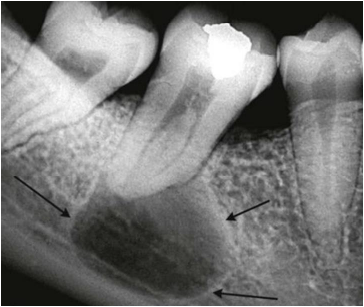

O exame radiográfico abaixo mostra imagem radiolúcida unilocular bem delimitada na região periapical do dente 47.

As setas pretas apontam para o halo radiopaco que circunda a lesão.

A imagem radiográfica apresentada é compatível com as seguintes lesões: